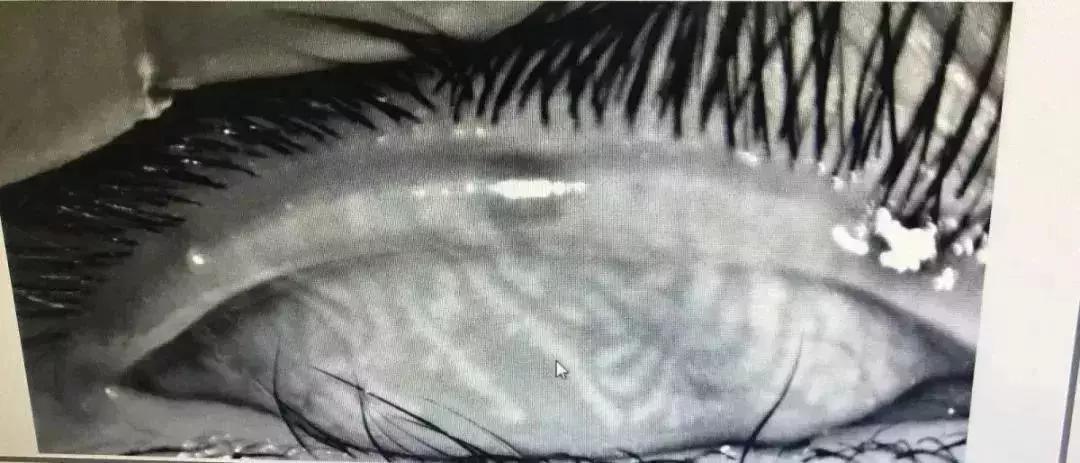

正常人的眼睑上大约有32个睑板腺,平行竖线状排列,分泌油脂用来湿润眼球,而小辛的睑板腺已经“扭曲”成网状,模糊不清,相当于中老年人水平,甚至比有些中老年更差,所以眼睛会感觉到刺痛、灼烧感进而睁不开,并且小辛的睑板腺功能彻底恢复是不可能的,只能靠治疗来缓解症状了。

小辛的睑板腺检查图